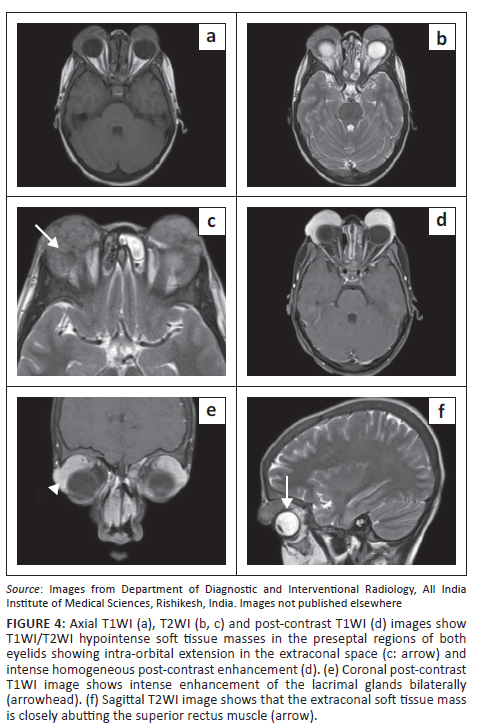

Assessing for the disease extent in the face and orbit and for any intracranial involvement, contrast enhanced MRI of the face, orbit and brain (Siemens Magnetom Aera 1.5 Tesla MRI, Germany) was acquired. The enlarged lymph nodes and salivary glands showed T2W hypointense signal and homogeneous post-contrast enhancement (Figure 3e, f). Homogeneously enhancing soft tissue masses were seen in the preseptal regions of the upper eyelids. The masses were hypointense on T1-weighted (T1WI) and T2-weighted (T2WI) sequences. No diffusion restriction was seen. There was extension into the extraconal compartment of the orbits, with abutment of the superior and lateral recti bilaterally. No intraconal or intracranial extension was seen. Both lacrimal glands were bulky showing T2W hypointense signal and homogeneous post-contrast enhancement (Figure 4).

Involvement of the orbit and eyelid can be seen in 7% - 10% of cases of RDD.4 It can be isolated or may be associated with skin or lymph node disease.11 Unlike the presented case, unilateral involvement of the orbit is more common. Patients can present with proptosis, limitation in the range of eye movements, swelling of the eyelids or decreased vision.2 An extraconal variably enhancing soft tissue mass with infiltration of the surrounding structures is the commonest manifestation on imaging.1,2,4 Involvement of the eyelids can be in the form of large preseptal (as in this case) or postseptal masses.2 Involvement of the lacrimal gland in RDD is a known entity and was seen in this case as bulky enhancing lacrimal glands. Involvement of the eye globe can also be rarely seen. Several cases of intracranial extension of the orbital masses have also been reported in RDD, though this is rare.1 A myriad of diseases that can mimic orbital involvement of RDD include lymphoma, orbital pseudotumor, sarcoidosis, haemangioma or lymphatic malformation like lymphangioma.2